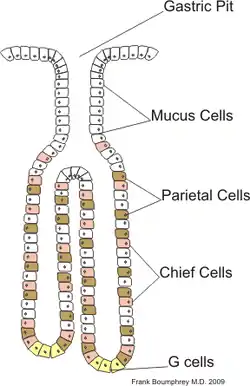

Microscopic Anatomy

The basic layout pattern holds true in the stomach, although the stomach has a third inner layer of oblique muscle fibers. The mucosal layer has numerous pits opening into the lumen, the mouths of the gastric glands. Some of these glands penetrate down into the submucosal layer.

Gastric Glands

The gastric glands secrete mucous, hydrochloric acid and enzymes into the stomach. They are located for the most part in the mucosal layer of the stomach, but some of the deeper gland penetrate into the submucosal layer, and secrete into the lumen via ducts. Several different secretory cells are found: mucous; parietal; chief cells; D cells; enterochafin cells; and G cells.

Mucous cells secrete both mucous and bicarbonate, substances that protect the stomach from auto-digestion. Parietal cells secrete hydrochloric acid (1-3 liters a day) which cause the pH in the stomach to fall as low as 1. Chief cells secrete the enzyme pepsinogen, which is activated to pepsin by the pH of the stomach. G cells produce gastrin, a hormone that promotes gastric acid secretions and stimulates the growth of the gastric mucosa.

The composition of the gastric glands varies throughout the stomach. In the fundus, the glands are more branched and contain all the different kinds of secretory cells. In the pyloric part of the stomach the glands are deeper and contain more mucous cells. Chief cells are found only in the fundus of the stomach, G cells are found mainly in the antrum, and the other cells are found in all areas.